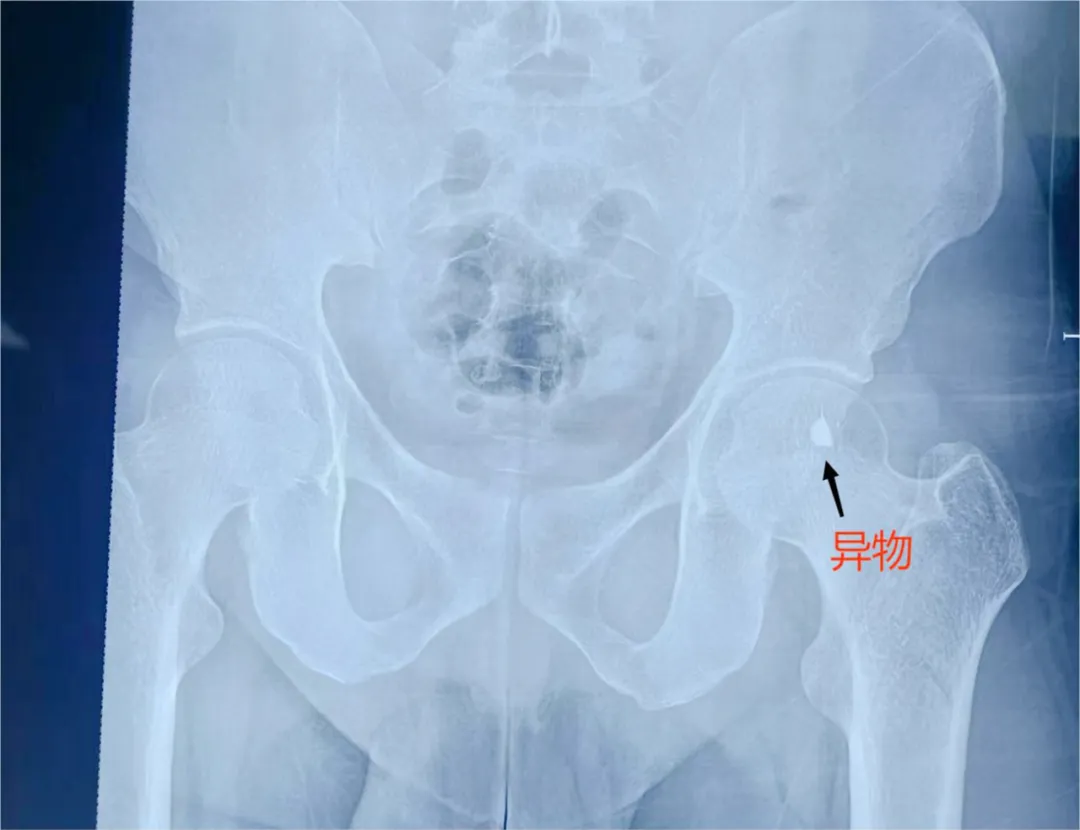

▲患者受伤部位影像资料

工厂同事紧急将他送往当地医院,当地医院完善骨盆X线片后,考虑铁片残留位置特殊,技术有限无法完成该类手术,于是又立即转到我市一所市级医院救治。该院完善盆腔增强CT检查后,发现异物十分靠近髂外动脉及股神经,相当于在血管神经周围存在一枚“定时炸弹”。该院认真研判患者病情后,认为如动脉搏动致铁皮割破血管及损伤神经,将严重危及患者生命,需立马行手术治疗,但考虑铁片非常靠近血管和神经,手术风险极大,最终建议转到我院治疗。面对这一突发状况,急诊医学科立即启动应急响应机制,医护人员迅速集结,准备迎接这场生命挑战。